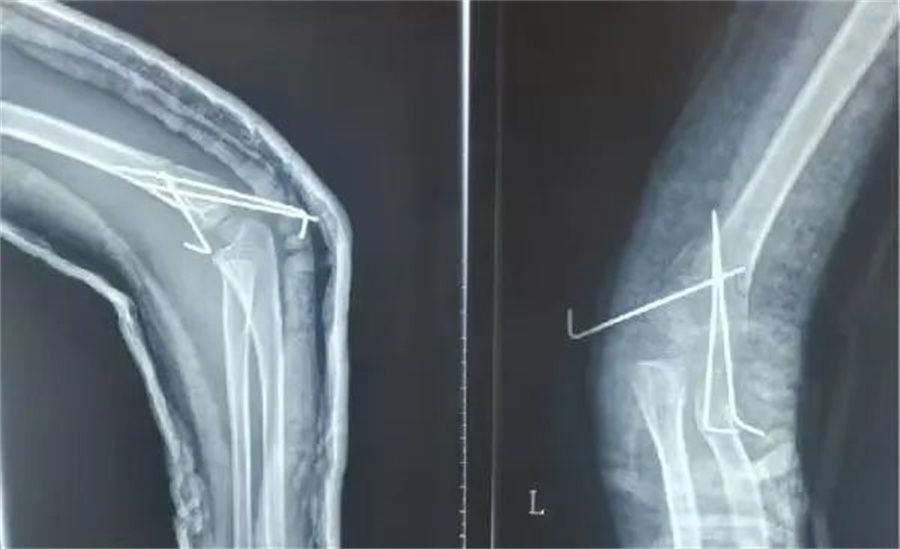

在各项检查指标都正常的情况下,儿童医院骨科的医护人员为他做了髁上骨折闭合复位术。

骨科医生在放射线下,一点一点摸索,最终复位成功,并且术后没有切口,没有瘢痕,4天后,孩子顺利出院。